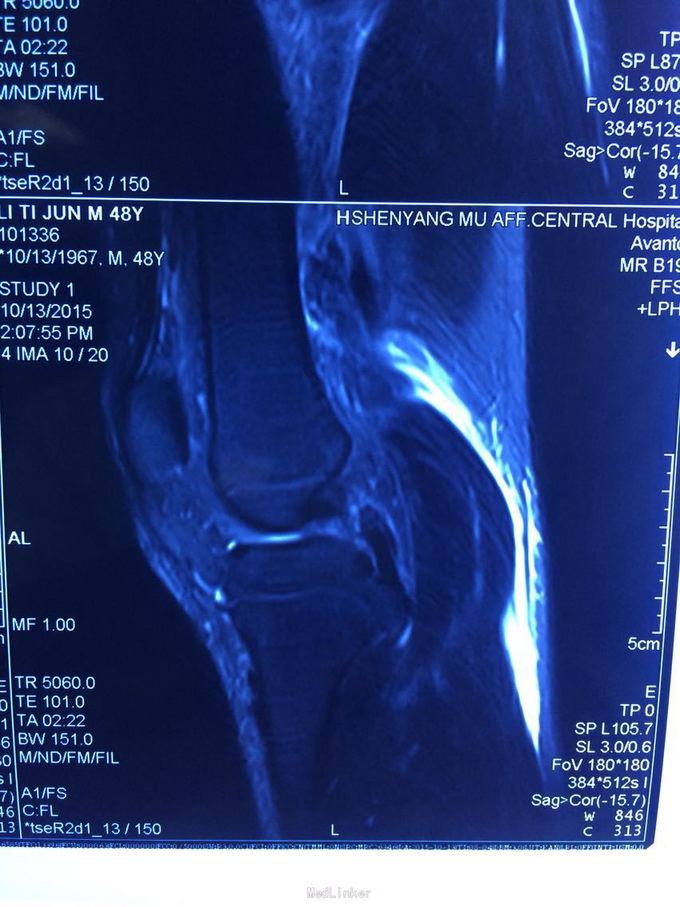

交通伤后膝关节疼痛,关节不稳。 患者交通伤,膝关节肿胀、疼痛,活动受限,肿胀消退后关节不稳。

查体:髌骨稳定,拉赫曼试验阴性,台阶征阳性3+,拨号征阴性,外翻0度阴性、30度阳性,内翻阴性。

诊断:膝关节多发韧带损伤,后交叉韧带、内侧副韧带 处理:给予关节镜下后交叉韧带重建,小切口修补内侧副韧带,取自体半腱股薄肌腱

后交叉韧带和内侧副韧带也有协同作用,后交叉韧带相比前交叉韧带术后容易出现松弛,故内侧副韧带也一期给予修补,后交叉韧带也可以选择inlay方法,但首次重建建议全镜下。